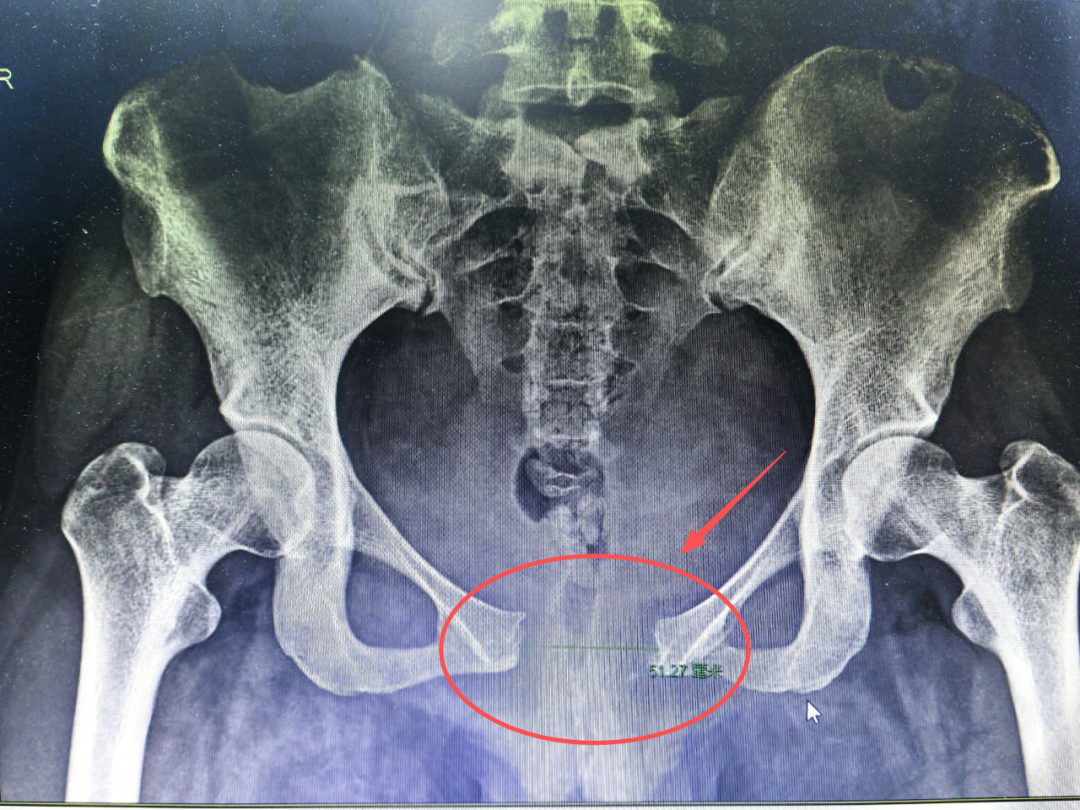

很多机构会用“耻骨联合分离”来制造焦虑,但事实上,真正的耻骨联合分离,是有明确症状和诊断标准的。

耻骨联合分离,图源:科室供图

医学上定义的耻骨联合分离,是指耻骨联合间隙大于10mm。这样的宝妈,会出现非常典型的症状:

而判断是否分离,必须通过拍片(X线、超声或CT)来确诊,医生也没有“透视眼”,单纯靠手摸是无法判断的。